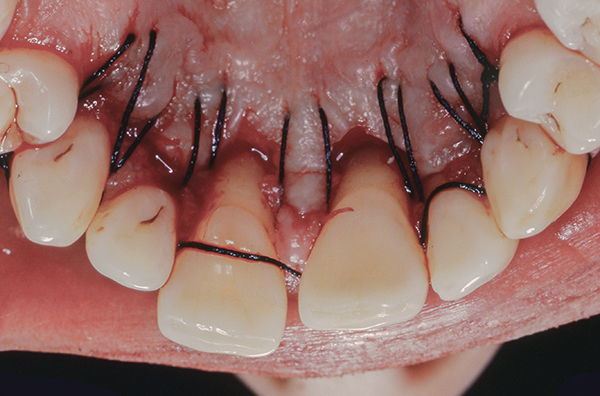

Horizontal Mattress Sutures After Molar Extractions Medizzy